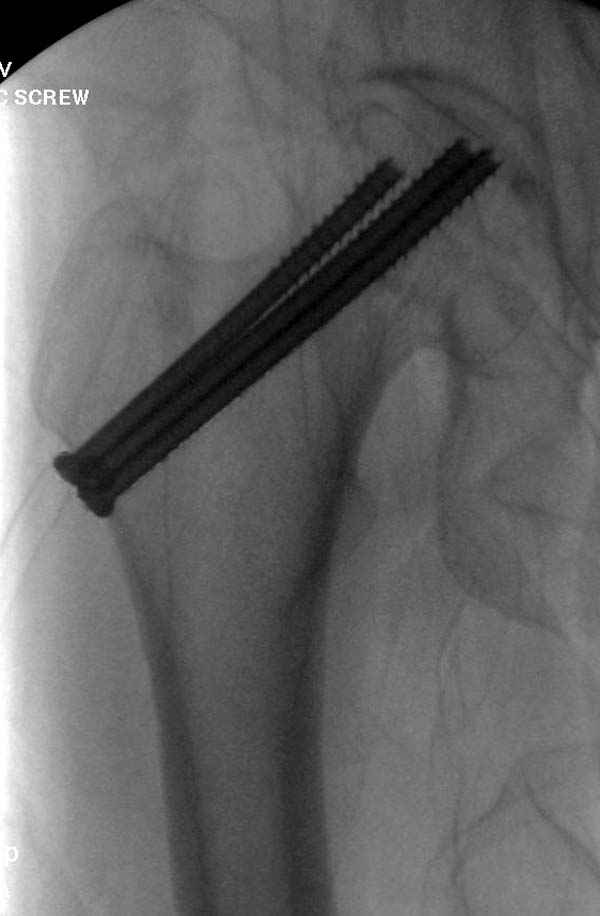

[Ortho] неполный перелом шейки

Профилактику дальнейшего раскола неполного перелома шейки провели тремя канюлированными шурупами.

На второй день после выписки упал дома. Снимки приложены. Коллеги рекомендуют удаление шурупа и вытяжение. Что делать?